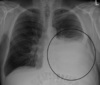

Bilateral pleural effusion

36